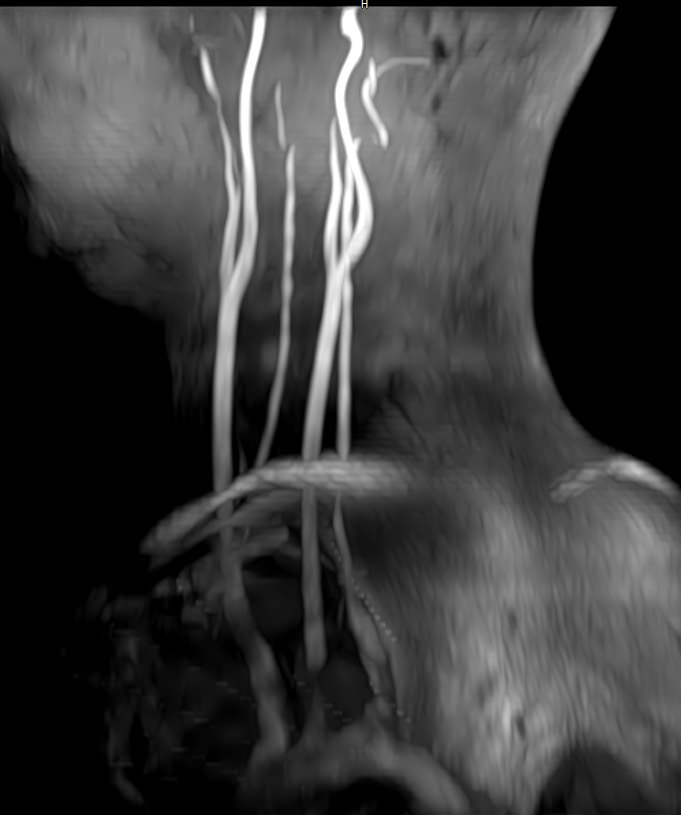

Кроме того, в области шеи проходят крупные кровеносные сосуды, кровоснабжающие все структуры головного мозга и мягких тканей головы. К ним относятся плечеголовной ствол, сонные и позвоночные артерии, которые далее в полости черепа соединяются между собой в Виллизиев круг. Это анатомическое образование позволяет компенсировать мозговой кровоток при патологических состояниях.

Часто различные нарушения в шейном отделе позвоночника приводят к ухудшению кровоснабжения головного мозга. Опухоли и дегенеративно-дистрофические заболевания шейного отдела позвоночника могут нарушать работу головного мозга. Атеросклеротические бляшки в сосудах шеи могут стать причиной преходящих нарушений мозгового кровообращения (транзиторных ишемических атак) и привести к развитию инсульта. Поэтому важно в комплексе детально визуализировать эти анатомические структуры вместе с оценкой состояния кровеносной системы головы и шеи.

Сканирование проводится на современном высокопольном магнитно-резонансном томографе закрытого типа TOSHIBA VANTAGE TITAN 1,5 Тесла. Магнитно-резонансный томограф производит послойное сканирование исследуемой зоны в разных плоскостях, затем при помощи компьютерных программ преобразует полученные данные в трехмерные изображения. При этом кровеносная система реконструируется как вместе с окружающими тканями, так и отдельно без них.

Что показывает МРТ головного мозга + МРТ шейного отдела позвоночника + МР-ангиография шеи и головного мозга

В рамках проведения данного комплексного исследования можно выявить:

• участки сужения, извитость, образование петель и перегибов сосудов;

• нарушения оттока крови за счет тромбообразования в венозном русле;

• ангиомы, сосудистые мальформации;